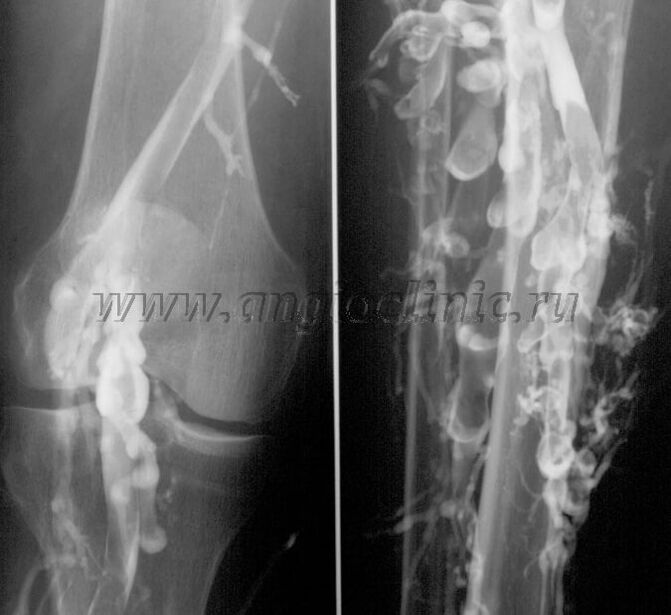

Kontrast-Velographie

Normalerweise reicht Ultraschall für eine vollständige Diagnose der Venenpathologie aus, in manchen Fällen ist es jedoch notwendig, den Zusammenhang zwischen dem Zustand des tiefen und oberflächlichen Venensystems zu untersuchen, insbesondere bei Rückfällen von Krampfadern und sekundären Krampfadern.

Um diese Probleme zu beheben, wird eine kontrastmittelverstärkte Röntgenuntersuchung eingesetzt. Die Stammvenen werden punktiert und Kontrastmittel verabreicht. Auf dem Monitor des Röntgengeräts wird die Kontrastbewegung beobachtet und alle notwendigen Untersuchungen und Projektionen durchgeführt. Derzeit wird die Venographie bei Krampfadern nur sehr selten eingesetzt.